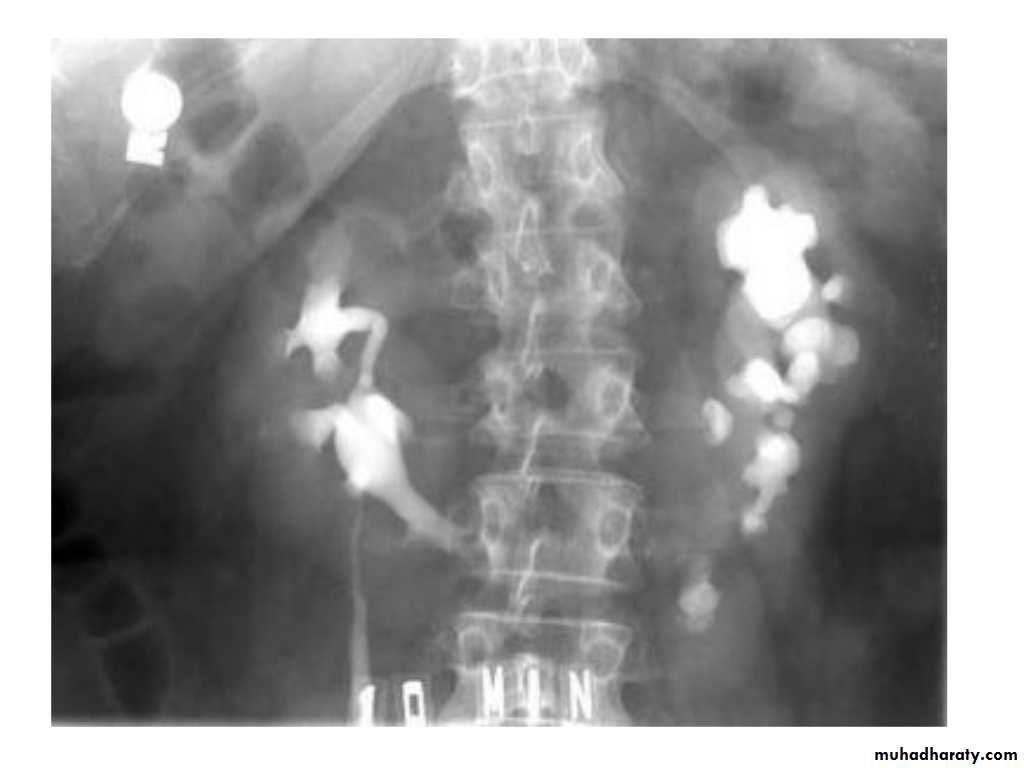

IVU shows

1. The kidneys at low position .2.Close to the spine with long axis parallel to the spine

3. Malrotation manifested by medially directed calyces.

4- The renal pelvis and ureters are anterior and lateral in position.

5- Hydronephrosis and calculi highly associated.